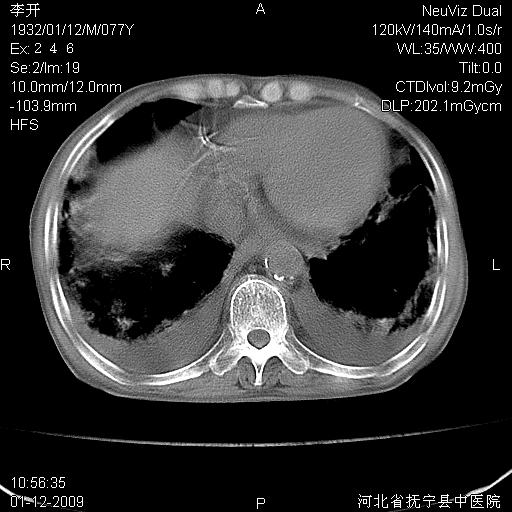

以下是引用黑白光影在2009-1-19 16:49:00的发言:[br]心衰肺水肿;心包、胸腔积液;冠脉钙化;肺部感染。